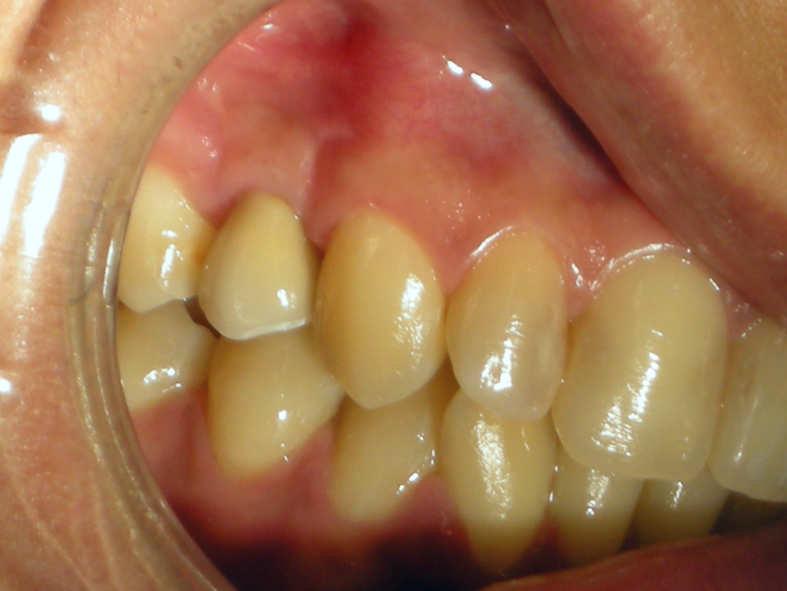

Sialolithiasis refers to the formation of stones in the salivary glands. Stones are most commonly found in the submandibular gland, where stones can obstruct Wharton's duct. It is frequently associated with chronic infection (Staphylococcus aureus, Streptococcus viridans) of the glands, dehydration (phenothiazines), Sjögren's syndrome and/or increased local levels of calcium, but in many cases can arise idiopathically. Pain, when present, usually originates from the floor of the mouth, although in many cases the stones cause only intermittent swelling.

Since chewing promotes release of saliva, symptoms tend to increase during meals. A palpable lump or visible swelling in the area of the gland is often noted.

Complications include persistent obstruction of the duct, leading to bacterial invasion, overgrowth and infection (sialoadenitis). This can require IV antibiotics such as nafcillin, and sometimes surgical drainage.